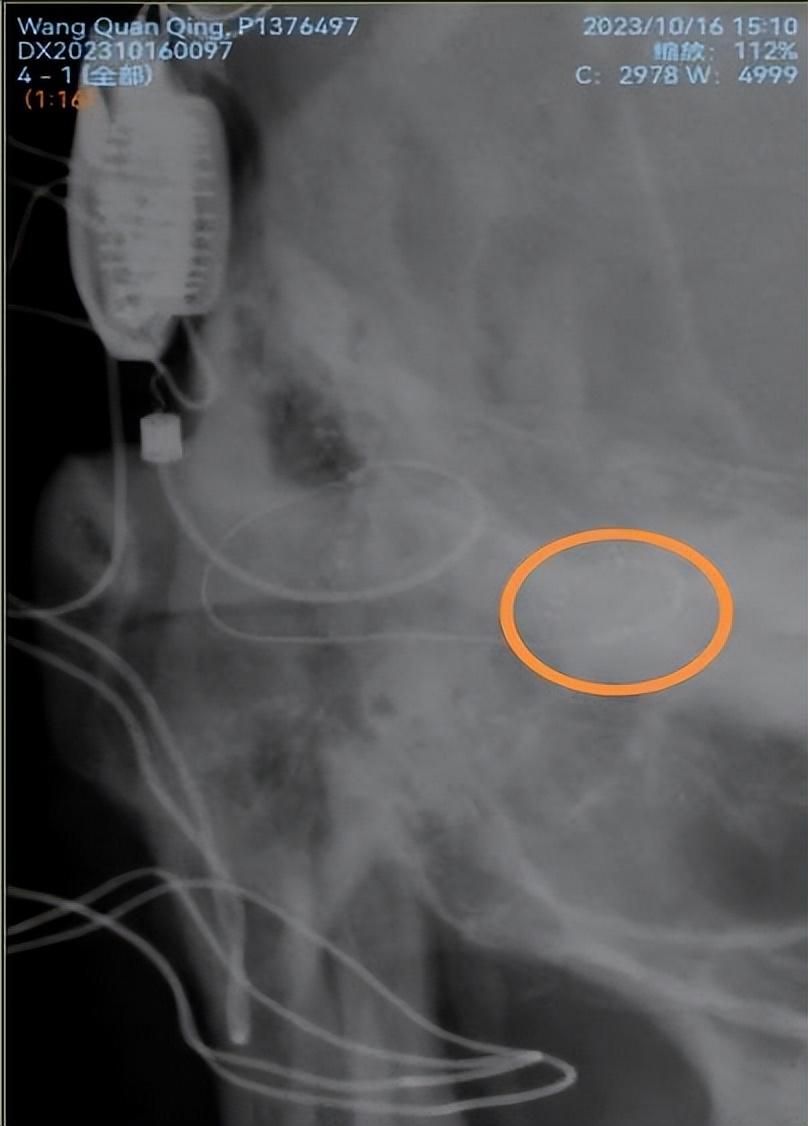

近日,太阳成集团tyc33455cc附属第一医院耳鼻咽喉科同一天给两例患有双侧极重度感音神经性耳聋而佩戴助听器无效的患者开展人工耳蜗植入术,这也是衡阳市自主开展的第一例和第二例人工耳蜗植入术。此手术在科室主任江青山教授的指导下,由科室副主任陈祖尧博士主刀完成,手术顺利,术中电极阻抗测量以及神经反应测试皆为正常,术后第二天的头颅X片提示植入电极在耳蜗内布阵良好,表明手术取得了成功。患者需要做的就是等待一个月以后的开机调试和言语康复。

术后颅骨X片显示耳蜗植入电极位置正常